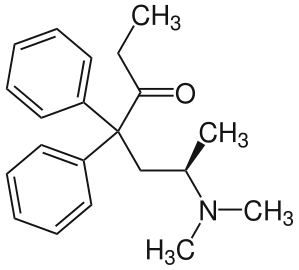

Amidones

Structures

| Amidones | ||||

|---|---|---|---|---|

|

|

|

Levoisomethadone Levoisomethadone | |

Noracetylmethadol Noracetylmethadol |

Levomethadone Levomethadone |

Methadone Methadone |

Methadone intermediate Methadone intermediate | |

Normethadone Normethadone |

Norpipanone Norpipanone |

Phenadoxone Phenadoxone |

Pipidone Pipidone | |